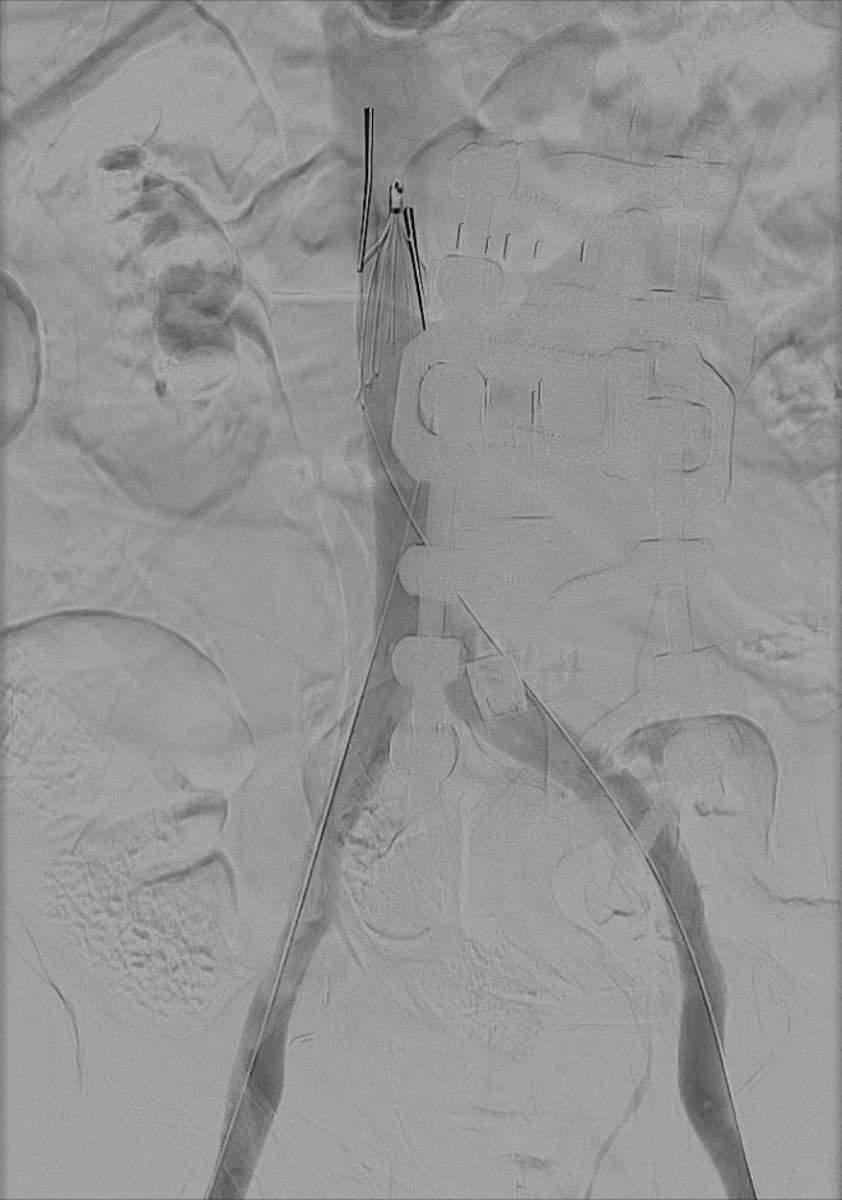

đ§đ©» Salvaging EVAR failure. Type Ia endoleak after EVAR is tough near renal arteries. This case shows success with F/B-EVAR using an integrated bifurcate graft, overcoming limitations of other designs while preserving seal & durability. đ https://t.co/Ms4lBRGmyO

#AortaEd